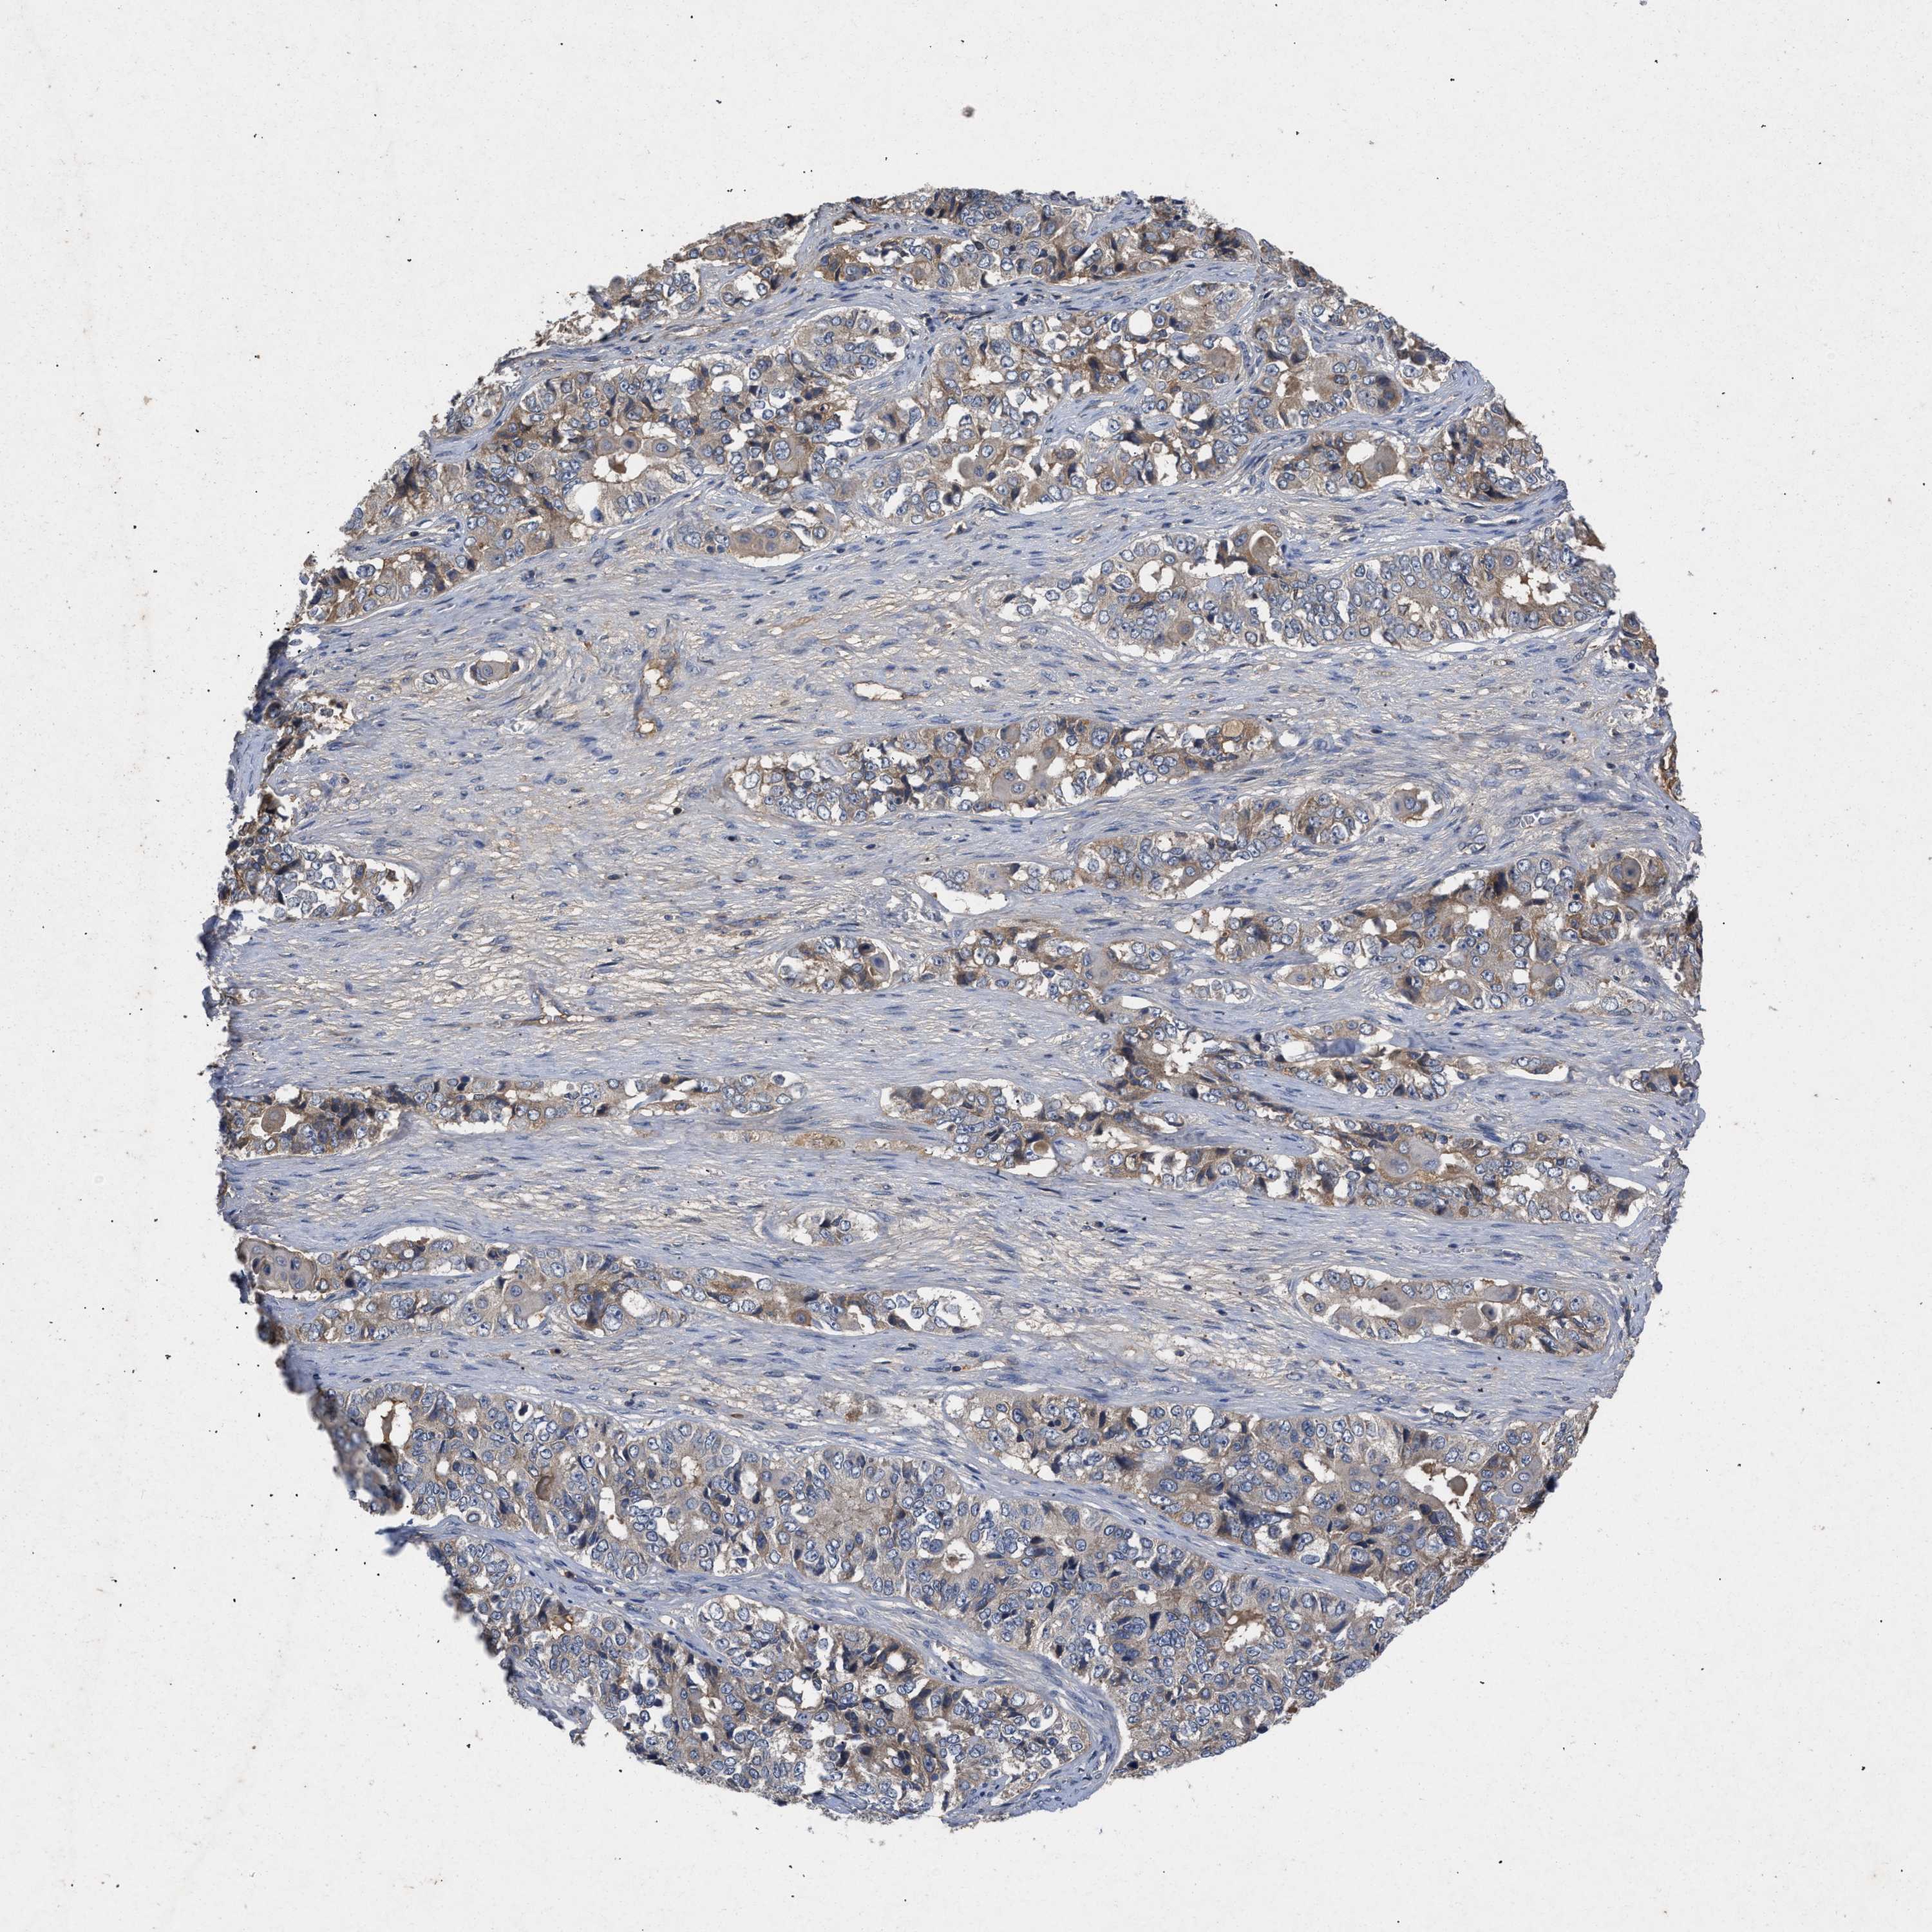

OVARIAN CANCER - Protein expressioni

A mouse-over function shows sample information and annotation data. Click on an image to view it in a full screen mode. Samples can be filtered based on level of antibody staining by selecting one or several of the following categories: high, medium, low and not detected. The assay and annotation is described here.

Note that samples used for immunohistochemistry by the Human Protein Atlas do not correspond to samples in the TCGA dataset.

Antibody stainingi

Antibody staining in the annotated cell types in the current human tissue is reported as not detected, low, medium, or high, based on conventional immunohistochemistry profiling in selected tissues. This score is based on the combination of the staining intensity and fraction of stained cells.

Each image is clickable and will lead to virtual microscopy that enables deeper exploration of all samples and also displays staining intensity scores, fraction scores and subcellular localization as well as patient and tissue information for each sample.

Antibody CAB018751

Antibody CAB034411

Cystadenocarcinoma, serous, NOS